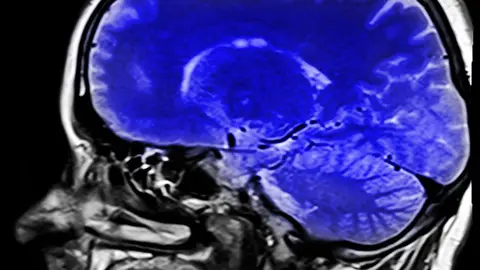

Modificaban los TACS y las resonancias para advertir de los fallos de seguridad en la industria hospitalaria y farmacéutica. Los médicos no se dieron cuenta en ninguna de las ocasiones.

Hackers israelís han manipulado varios TACS y resonancias para advertir fallos de seguridad en la industria hospitalaria y farmacéutica.

Lo hicieron en dos ocasiones, mostraron tumores cancerígenos y en ambas, los radiólogos no se dieron cuenta de que la máquina mostraba resultados modificados.